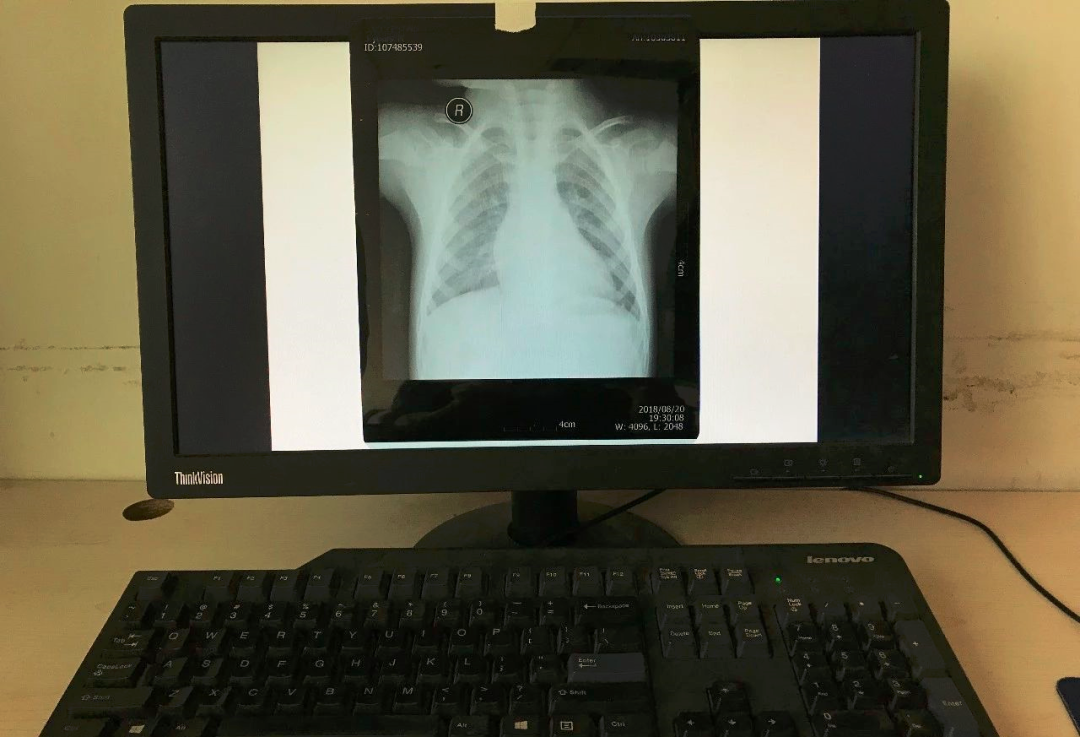

如果家里有电脑(台式机或笔记本电脑均可),也可以使用电脑显示器调白色后进行拍摄。使用电脑拍摄的时候,在电脑打开幻灯软件Powerpoint (PPT),新建一个空白文档,纯白色的,然后把该文档全屏播放模式下,即可实现全屏白色。

将准备好的白纸贴于窗户玻璃上,然后将X光片或磁共振或CT片子贴于白纸上。如果用的是电脑显示器翻拍片子,按照第1条将显示屏变白色后,将片子贴于显示器上进行拍照。拍照时一定要正对着片子拍,注意横平竖直,拍端正了,不要拍歪斜了。

ct打印胶片怎么用远程就医、转院就医时,CT核磁DICOM电子胶片的重要性!【就医知识】_https://www.jmylbn.com_新闻资讯_第5张

ct打印胶片怎么用远程就医、转院就医时,CT核磁DICOM电子胶片的重要性!【就医知识】_https://www.jmylbn.com_新闻资讯_第6张

ct打印胶片怎么用远程就医、转院就医时,CT核磁DICOM电子胶片的重要性!【就医知识】_https://www.jmylbn.com_新闻资讯_第7张

ct打印胶片怎么用远程就医、转院就医时,CT核磁DICOM电子胶片的重要性!【就医知识】_https://www.jmylbn.com_新闻资讯_第8张